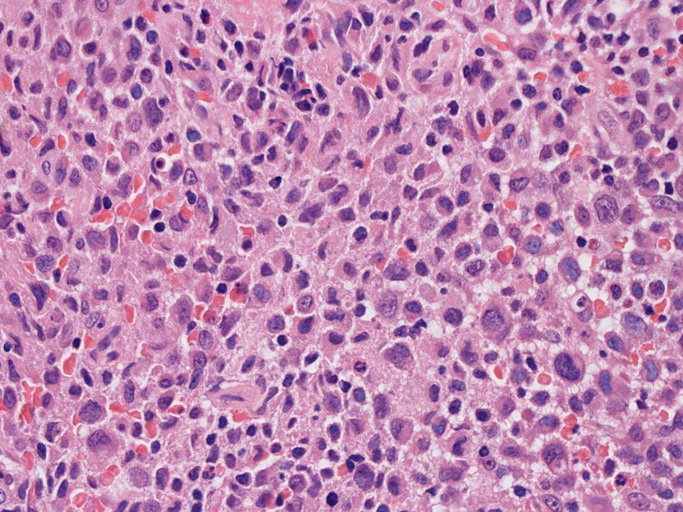

光顕所見(Fig.01~Fig.09)

皮膚に異型細胞の浸潤がみられる。異型細胞は表皮内に浸潤するほか、表皮真皮境界部, 真皮, 皮下脂肪組織にもびまん, 結節様の浸潤所見を示す。血管周囲に浸潤、集蔟する所見も多く見られる。 増殖浸潤細胞の核には類円形や腎臓形, またはへこみ, 切れ込み, 溝などを有する多型な核が認められる。クロマチンは粗でvesicularな核が多い。核小体の明らかな核もある。好エオジン性の核内封入体様構造も少数に見られた。mitosisは容易に認められる。hyperchromaticな多型核, bizzarreな細胞が高頻度に認められ異型度は高いと考えられる。細胞質は境界不明瞭, 淡明または泡沫様の 好エオジン性胞体である。

免疫染色 浸潤細胞はCD1a+, S100+, Langerin+, HLA-DR+, CD4+, CD45+, CD68+. MIB-1 index:24.4%

Speaker's Pathological Diagnosis: Langerhans cell sarcoma, skin, rt. knee, biopsy